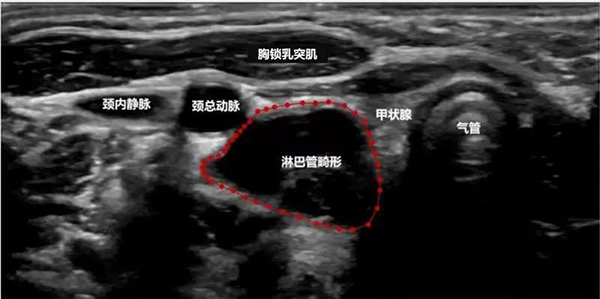

由于淋巴管畸形可发生在身体的任何部位,大多数发生在头颈部,其次为腋窝、纵膈及四肢。通常进行超声、磁共振、CT、诊断性抽液等检查,必要时依据情况进行穿刺活检,基本可以确诊。当怀疑患有淋巴管畸形时,应首先做超声检查,查清楚病变的部位、性质、大小及与周围组织的关系,评估是否需要治疗以及如何治疗。

淋巴管畸形超声:精准定位病灶部位范围以及与周边脏器的关系

超声难以确诊的病例,或病变周围结构较复杂(如在颈部、纵隔等部位)以及位置较深(如在腹腔、盆腔等部位)治疗难度大、风险高时,往往需加做磁共振检查,更精确评估病情。当影像学检查难以诊断时,也可行诊断性穿刺,若穿刺抽出淡黄色清亮淋巴液即可诊断为淋巴管畸形,若抽出陈旧性血液结合细胞学检查可诊断为淋巴管瘤伴出血。